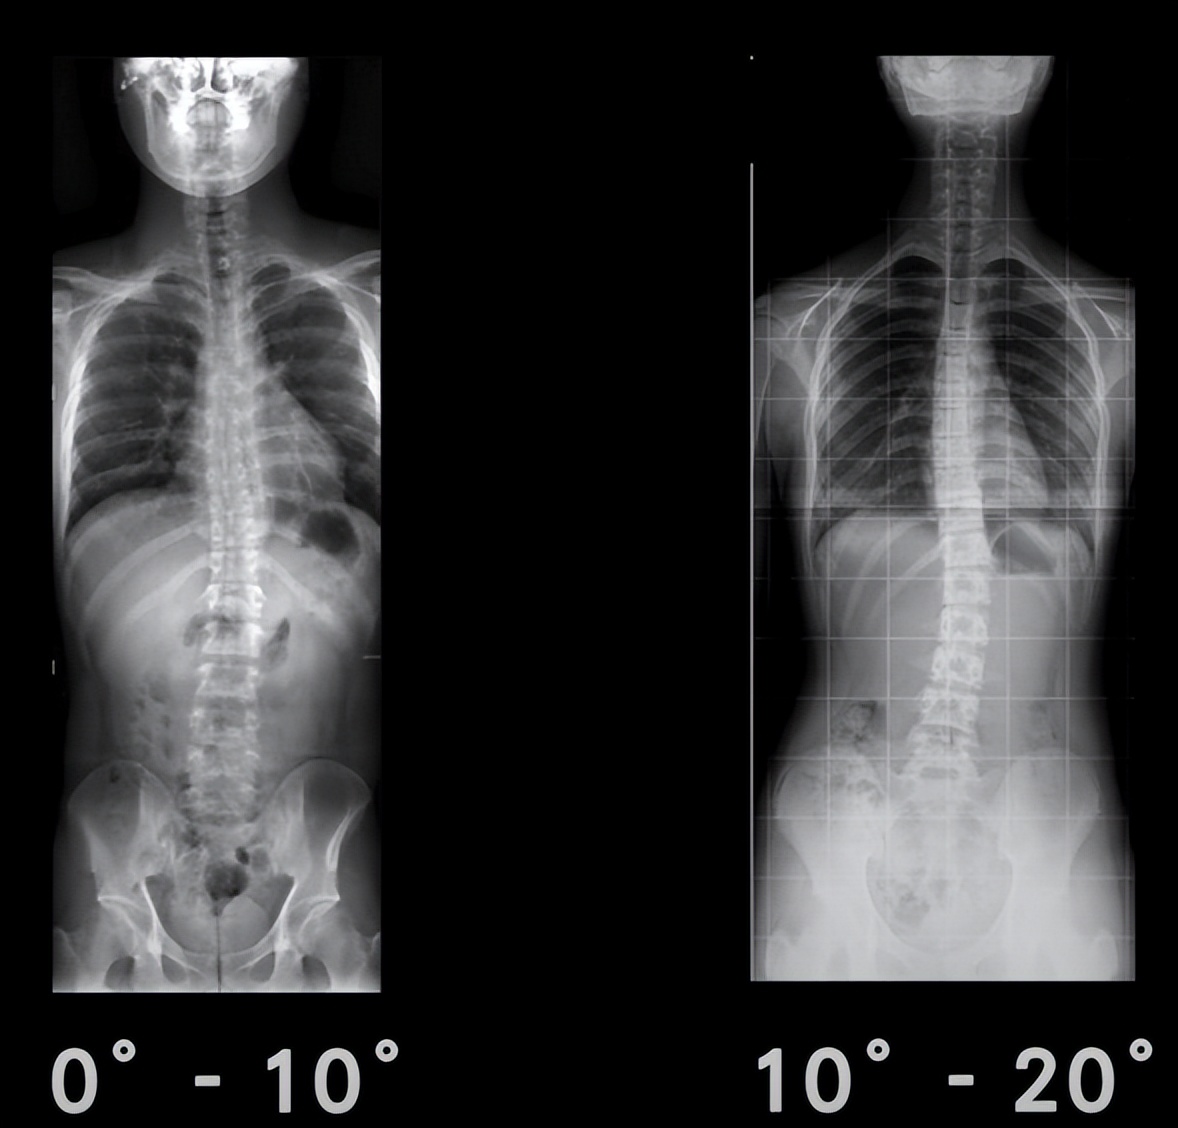

二、如何判断脊柱侧弯的严重程度?

X光显示0°-10°,10°-20°为轻微侧弯,一般25°一下相对就比较轻微,20°-40°是重度侧弯,40°以上就相对严重。